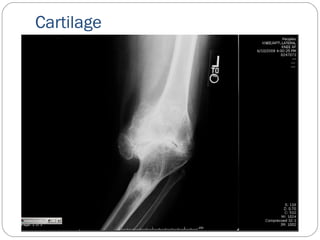

A-B-C-D

C- Cartilage- sufficient cartilage space

Cartilage